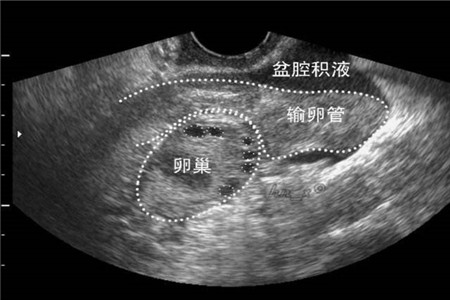

其实很多备孕的人都是很担忧的,那会不会能。其实是会影响到怀孕的。因为患有盆腔积液的朋友都会造成输卵管被堵住或者是粘连的情况从而影响到了怀孕。

其实一般的盆腔积液可以通过物理方式,但严重一点的比如说造成了输卵管积水或者是囊肿的时候就需要通过手术的来治疗。一般来说综合性的治疗是比较稳妥的,可以避免复发。